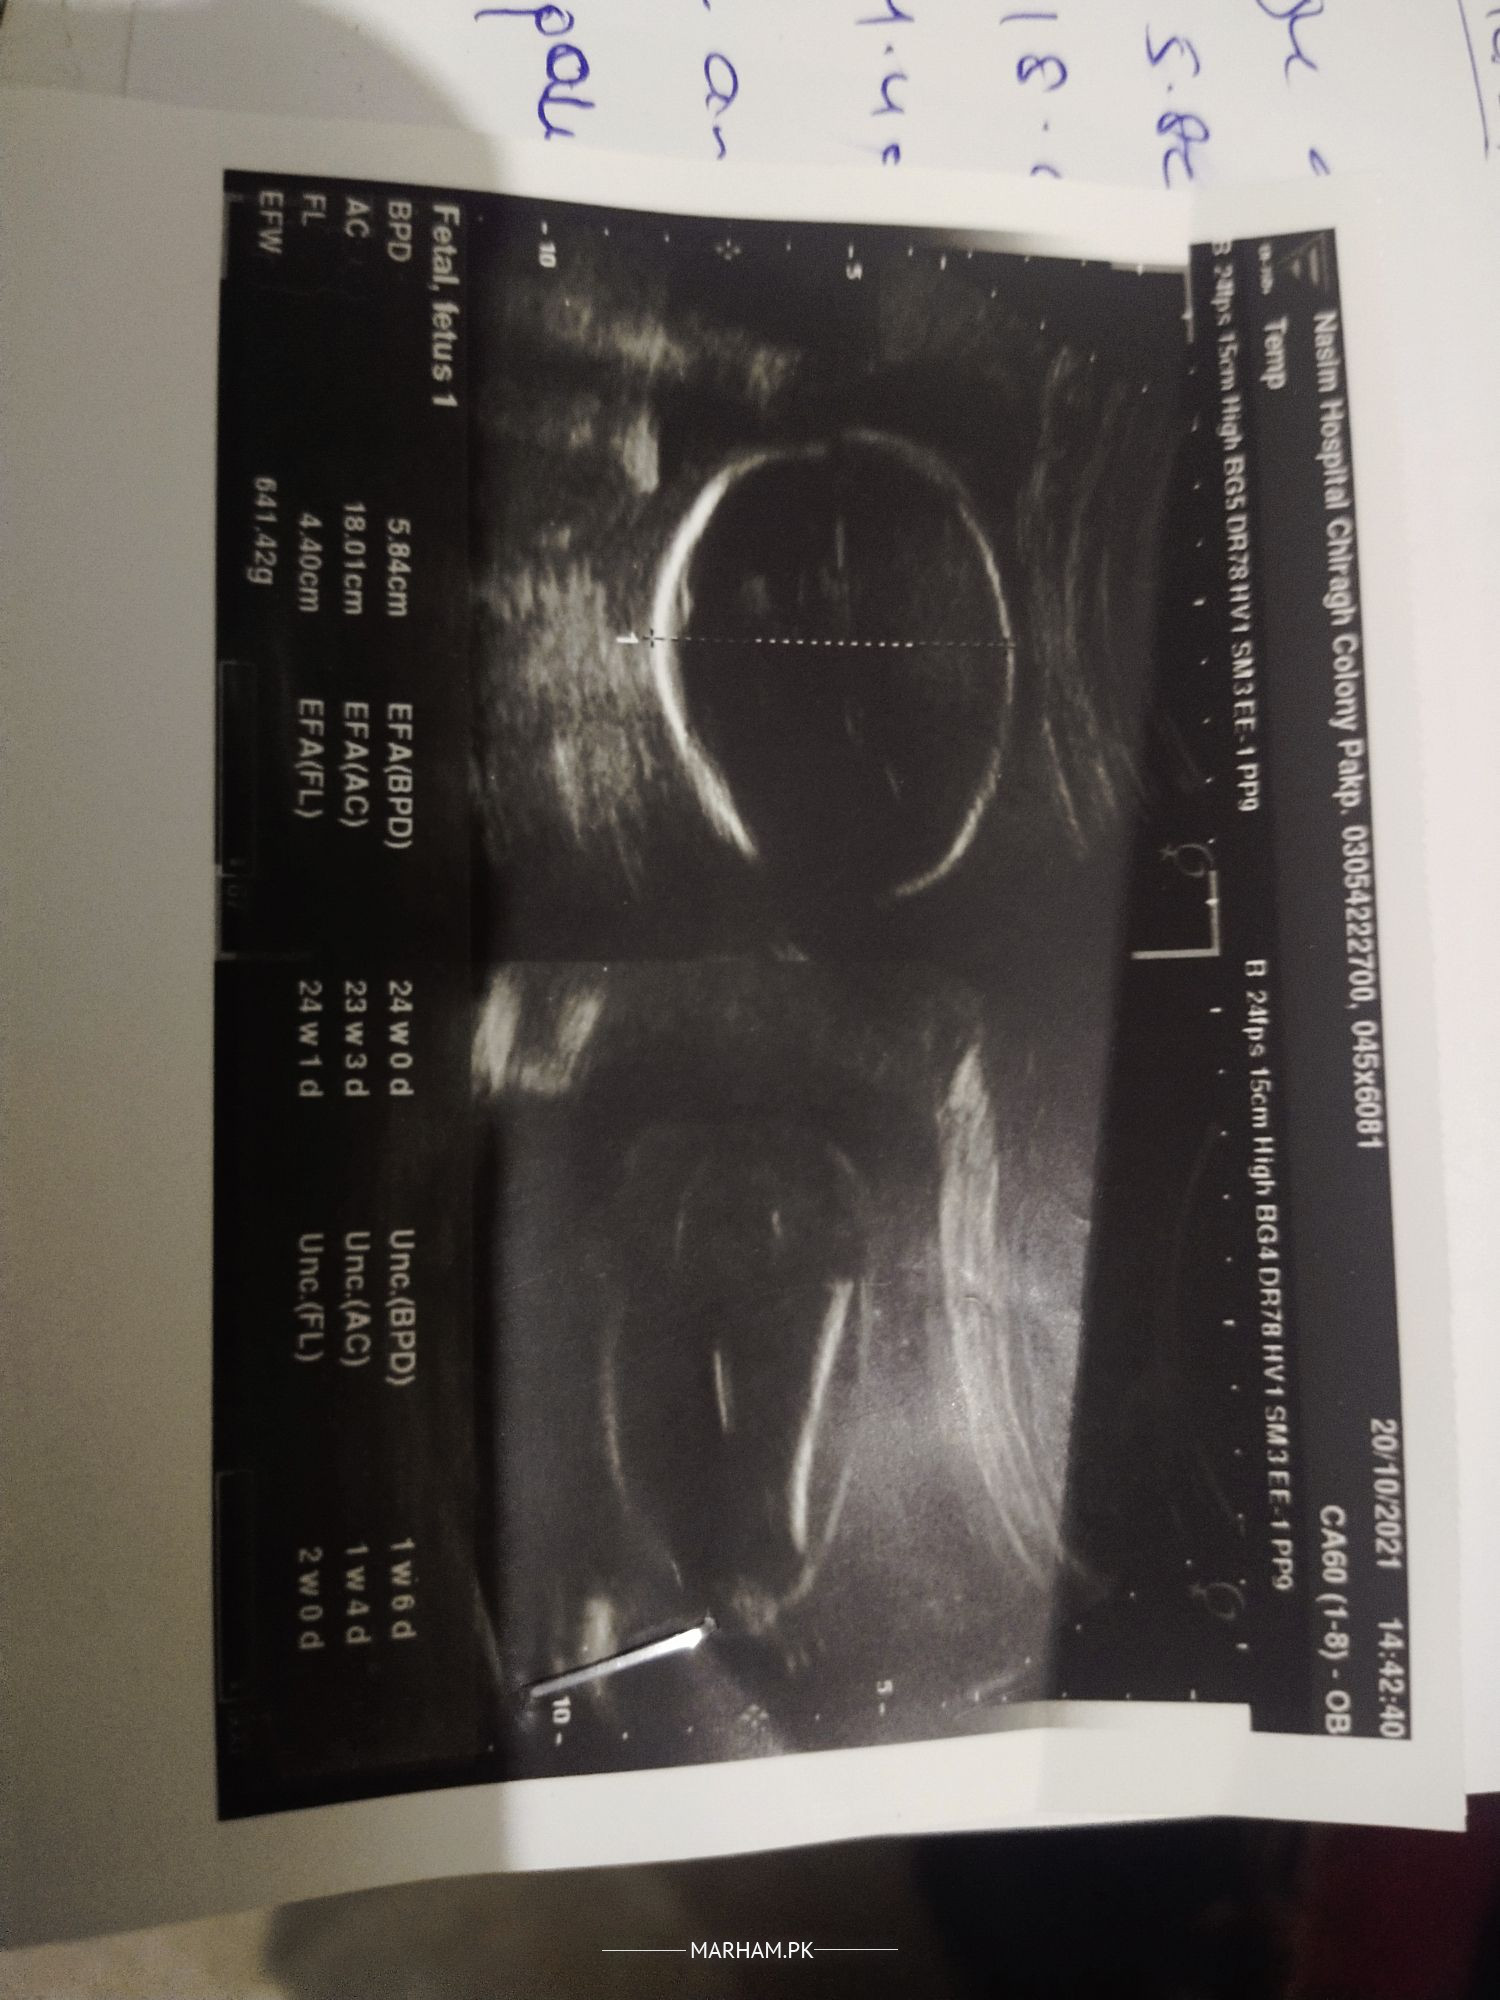

Aoa I have a question Kindly Ap bta skti ess ultrasound sy k Baby boy hy ya girl hy keonky mri doctor sahiba Ny 2 bar pocha unsy woh kehti han k Jo bhi hy Allah ko malom but mjhy malom krna please inform me

It would be better to ask the person who actually performed the scan ? The images you posted are not meant for gender identification ?